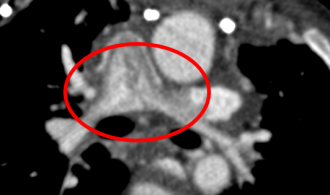

MAPCA症例 4本のMAPCAが有する症例